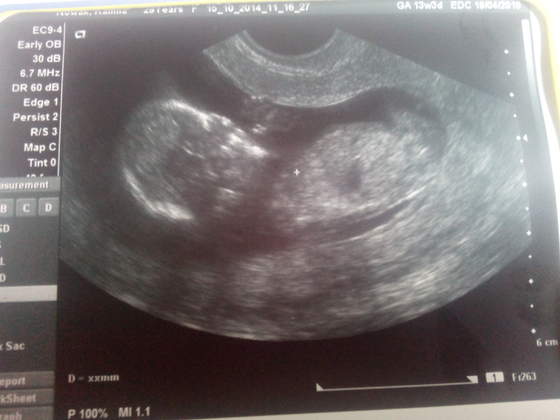

A to moje Motylki :-) przepraszam za kiepską jakość:zawstydzona/y:

14tc razem.jpg14tc ser1.jpg14tc ser2.jpg